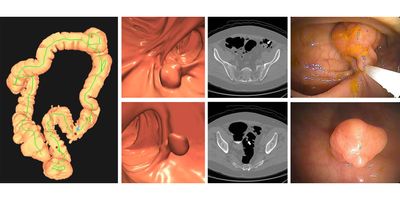

NIH modeling study looked at the individual and combined impacts of cancer prevention, screening, and treatment